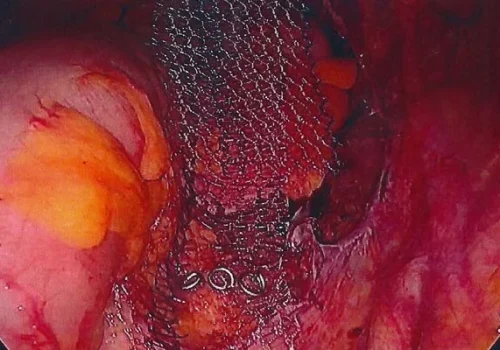

Procedure

She subsequently underwent Total Laparoscopic Hysterectomy and Laparoscopic Mesh Sacral Colposuspension.